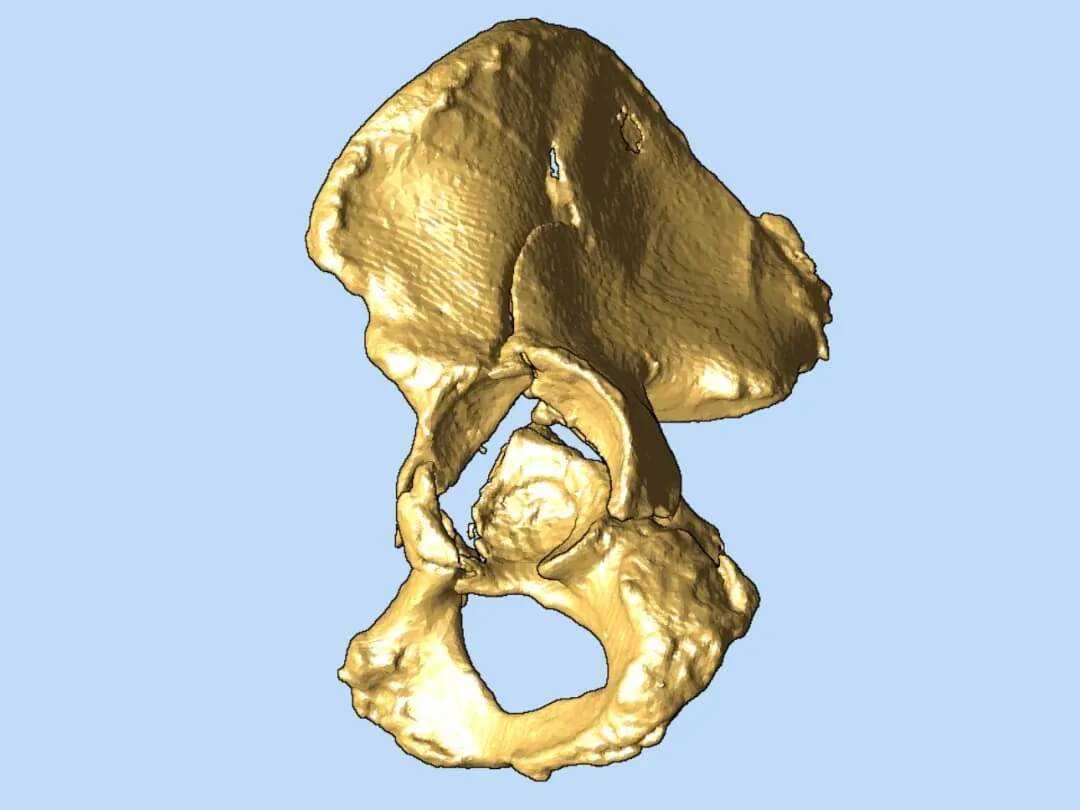

在腔靜脈濾器成功植入,患者安全度過血栓脫落風(fēng)險的高危期后,羅軍團(tuán)隊(duì)將利用先進(jìn)的3D打印技術(shù),為患者量身定制骨盆骨折修復(fù)方案。基于患者CT數(shù)據(jù)打印出的1:1精準(zhǔn)骨盆模型,能讓醫(yī)生在術(shù)前清晰掌握粉碎骨塊的形態(tài)、位置,實(shí)現(xiàn)極致的手術(shù)可視化和方案個性化,顯著提高手術(shù)精準(zhǔn)度、減少創(chuàng)傷、縮短手術(shù)時間,最終目的是促進(jìn)患者獲得最佳的功能恢復(fù)。